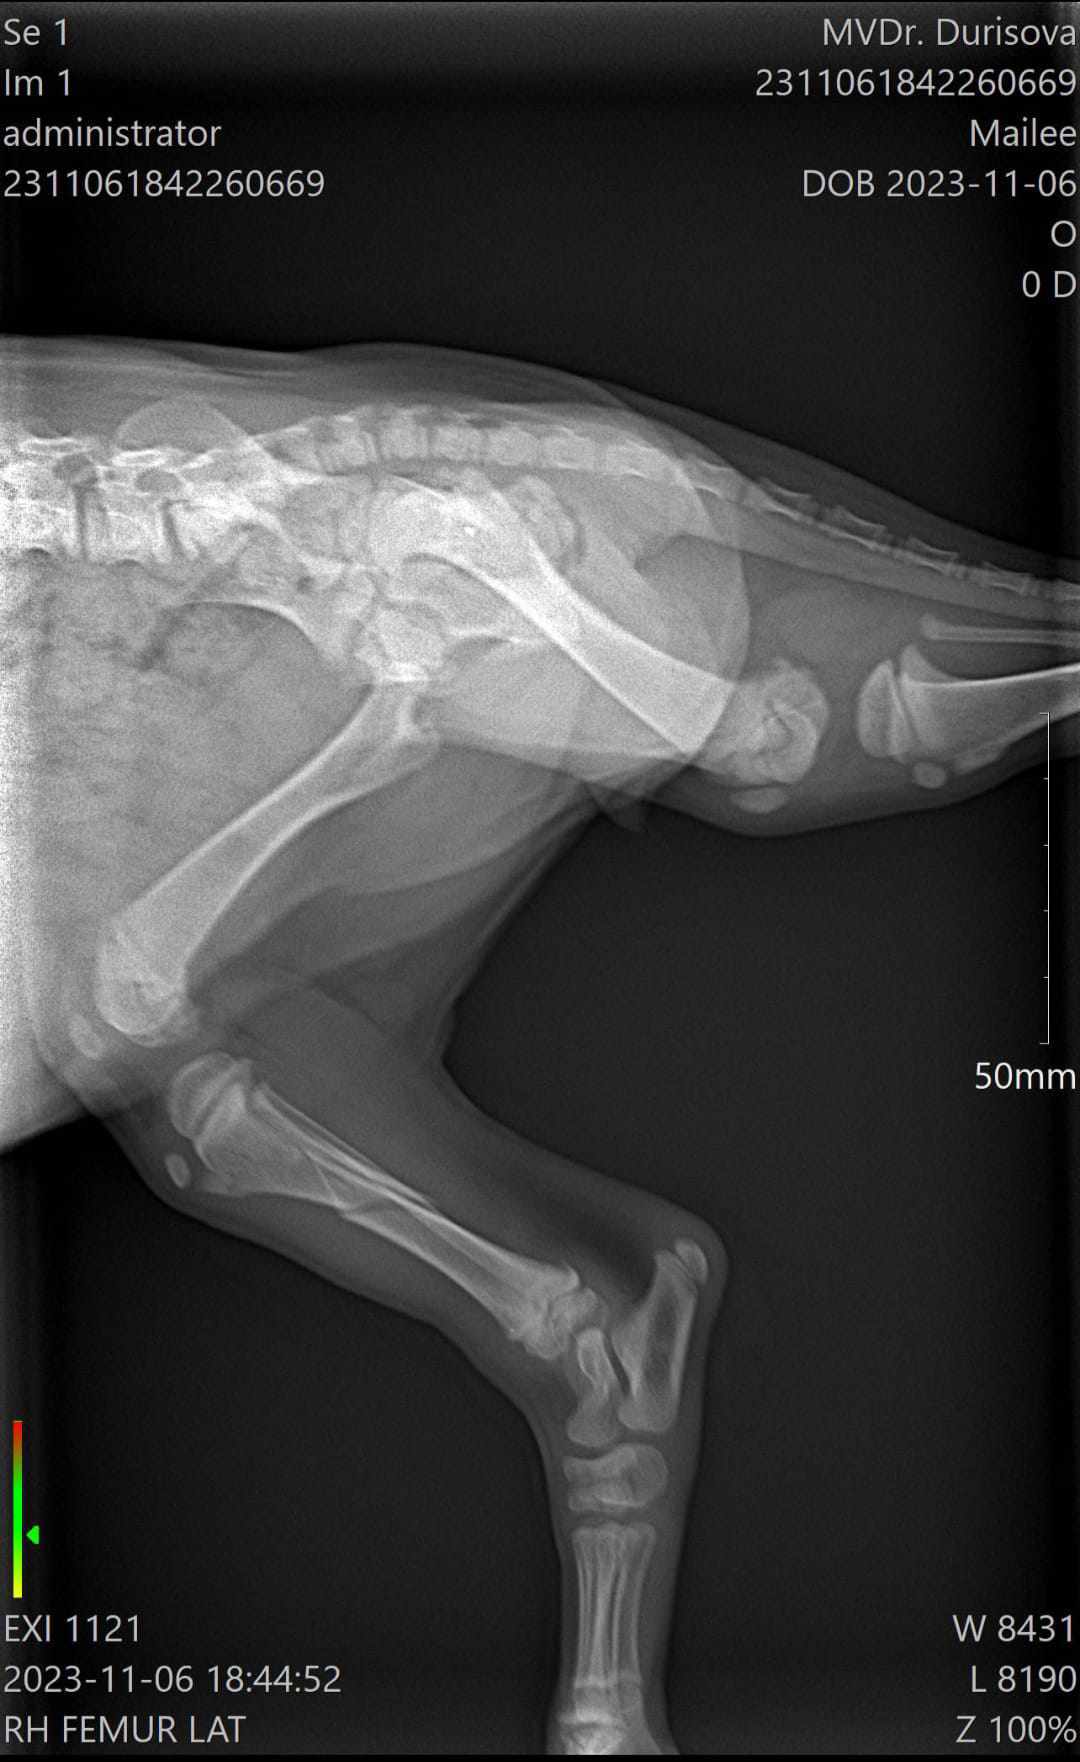

Mailee je roztomilá holčička údajně plemena welsh springer španěla. Má zlomenou zadní pravou packu. Zlomenina je spirálová , což je paradoxně ta lepší zpráva, protože by se měla dobře hojit. Podstoupila na klinice operaci, kde se zlomenina zafixovala. Mailee čekají převazy, kontrolní rentgeny a vyndání stehů. Dostává léky na bolest každý den a sirup. Po operaci hodně plakala, ale už pomalu začíná řádit. Potřebuje kontakt ostatních dvounohých i čtyřnohých společníků, protože byla brzy odstavena od maminky. Jakmile je v blízkosti psího parťáka, je klidná a usne. Dle veterináře by zlomenina měla být do dvou měsíců v pořádku a nemělo by jí to nijak v budoucnu omezovat.

• zlomená pravá zadní packa - operována